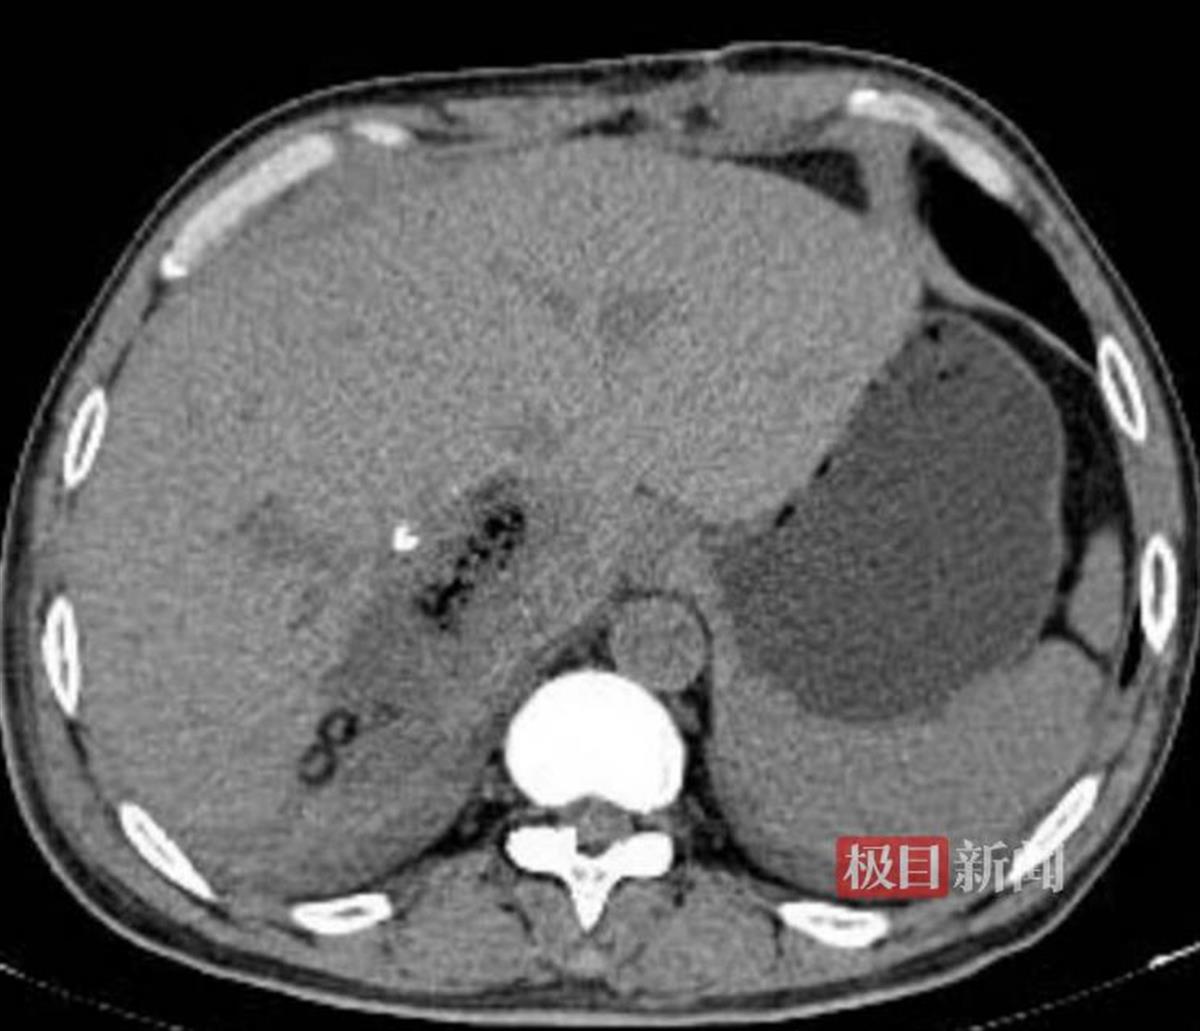

术后一周复查,残肝体积增生

术后3个月复查,肝脏未见异常

胡少勃介绍,即使是60岁的年纪,患者肝脏的再生能力仍很强,在去除肿瘤后,肝脏重约1907克,也比正常的肝脏体积大,完全可以满足机体的需要。